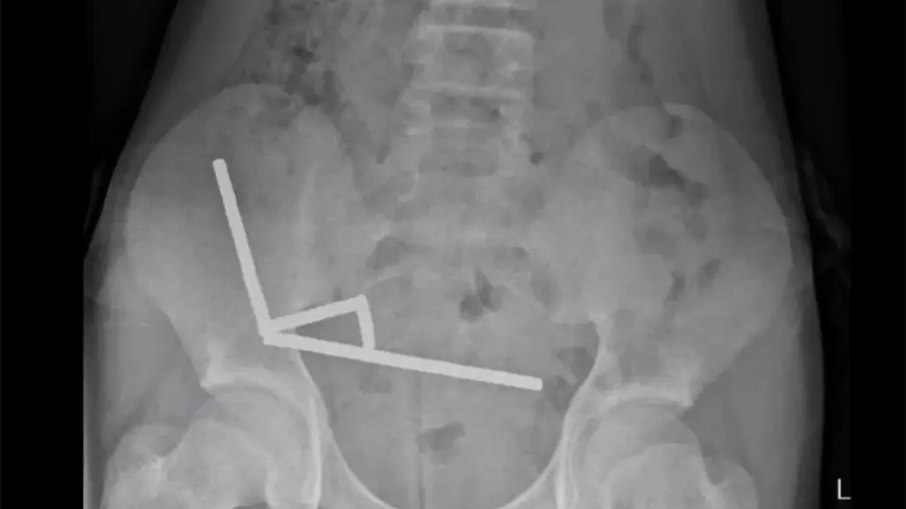

Raio X do estômago do menino

Exames de raio-X mostraram quatro fileiras de ímãs presos em diferentes partes do intestino, que se atraíam entre si e comprimiam o tecido intestinal, cortando o fluxo de sangue. Essa pressão provocou várias áreas de necrose, ou seja, morte do revestimento intestinal, o que exigiu uma cirurgia de emergência para a retirada dos ímãs e das partes afetadas do intestino.

Segundo o relatório médico, os ímãs mediam cerca de 5 por 2 milímetros e se alinharam em quatro correntes dentro do intestino. A força magnética fez com que partes do órgão se grudassem, comprimindo o tecido entre elas. Os cirurgiões alertaram que pacientes submetidos a esse tipo de procedimento podem desenvolver complicações duradouras, como obstruções intestinais, hérnias e dores abdominais crônicas.